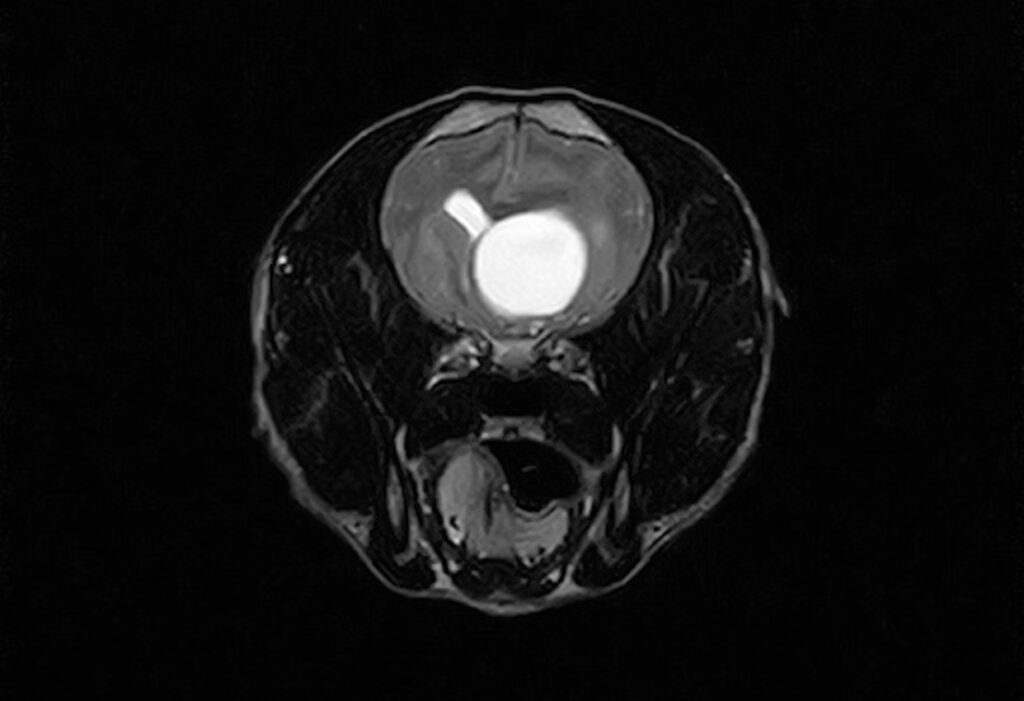

来院時、歩行は可能でしたが、四肢の固有受容(CP=姿勢反応)が低下し、趾端の過敏がみられました。凶暴性のため一部の評価が難しい項目もありましたが、視覚は保たれていました。神経学的検査所見から前頭葉領域の障害を疑い、MRI検査で左側に巨大な嚢胞を伴う腫瘍性病変が示唆されました。

術直後MRIでは嚢胞の退縮と、脳が正常位置に戻る兆候が確認されました。術後は数日間の入院下で創部や包帯の管理を行い、抜糸後に退院としました。今後は囊胞の再発や腫瘍の再増生、周辺脳浮腫の評価のため、数ヶ月後のMRI再検が推奨されます。

▲pre

▲after